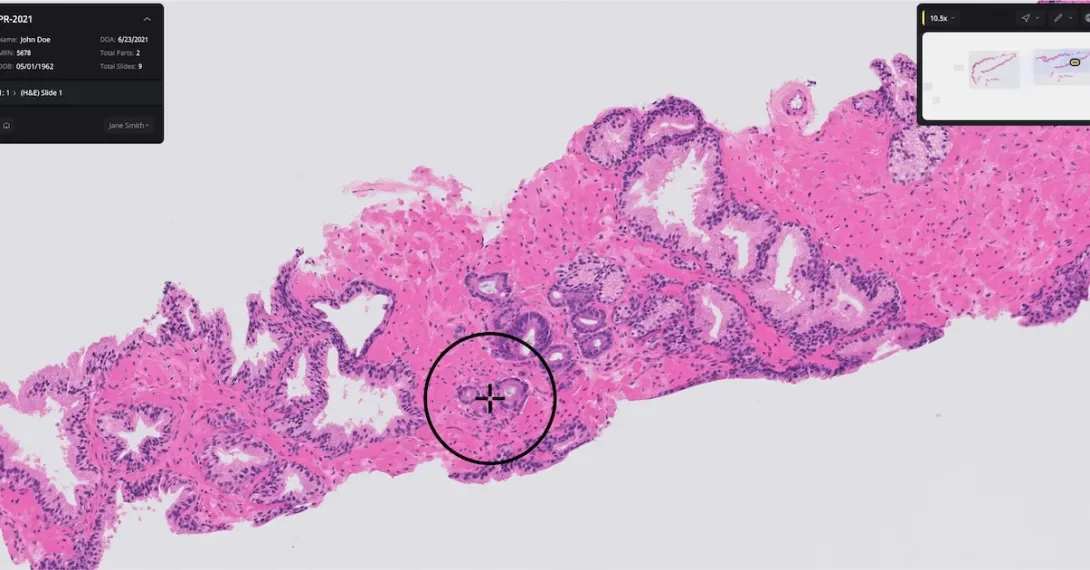

The Paige Prostate software analyzes digitized biopsy slides and identifies areas that could be cancerous for the pathologist to review further.

Authorization for Paige Prostate was based on a clinical study where 16 pathologists examined 527 prostate biopsy slides. The software improved the pathologists’ ability to detect cancer on individual slide images by an average of 7.3% (from 89.5% to 96.8%).

Further, pathologists using Paige’s software had a 70% reduction in false-negative diagnoses and a 24% reduction in false-positive diagnoses. Paige Prostate also helped boost nonspecialist pathologists’ diagnostic accuracy to the same level as prostate specialists who were not using the software.

“Pathologists examine biopsies of tissue suspected for diseases, such as prostate cancer, every day. Identifying areas of concern on the biopsy image can help pathologists make a diagnosis that informs the appropriate treatment,” Dr. Tim Stenzel, director of the FDA’s Office of In Vitro Diagnostics and Radiological Health, said in a statement.